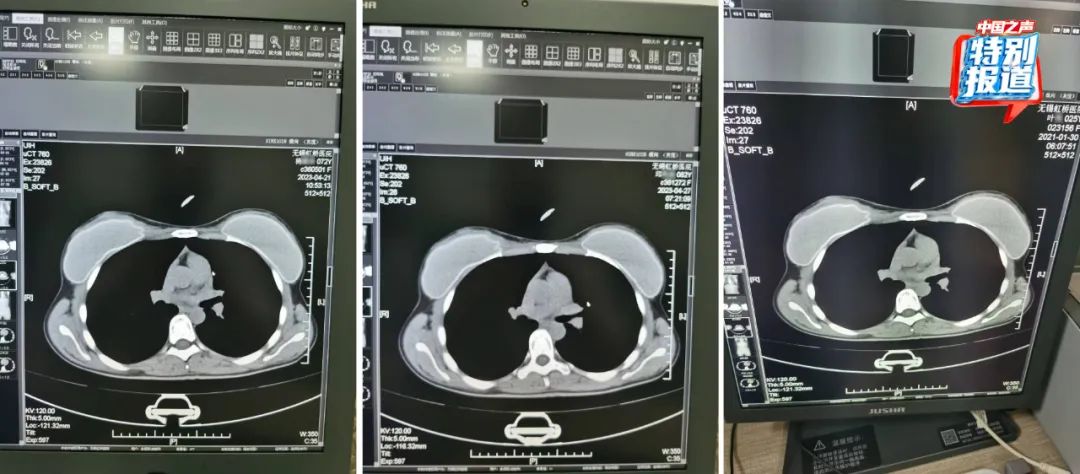

多名患者和他人影像高度相似

在被举报的病历中,杨某某(72岁)和邱某某(62岁)的病历里,有根据所拍片子的情况做出的诊断,却找不到对应的影像。6月份又查到了她们的CT影像,按照系统记录,这两人都是2023年4月做的胸部CT,片子上能清晰看出,两位患者的吊坠形状、大小和位置都基本一致。

不仅这两位上了年纪的患者CT影像类似,朱成刚比对发现,2021年在他们科做过CT的25岁女性叶某的片子上,也有看起来极为相似的吊坠,肉眼看,三人的片子几乎一模一样。

类似这样看上去雷同程度很高的片子,还有不少。系统显示:

患者李某某在2023年4月28日拍摄了胸部CT,她的影像与实际患者刘某在2024年2月的检查影像看起来高度相似。

74岁的患者莫某在2023年4月27日拍摄了胸部和颈椎的CT,她的片子看起来和实际患者37岁的马某某在2023年11月拍的片子高度相似,片子里能直观看到项链都一模一样。